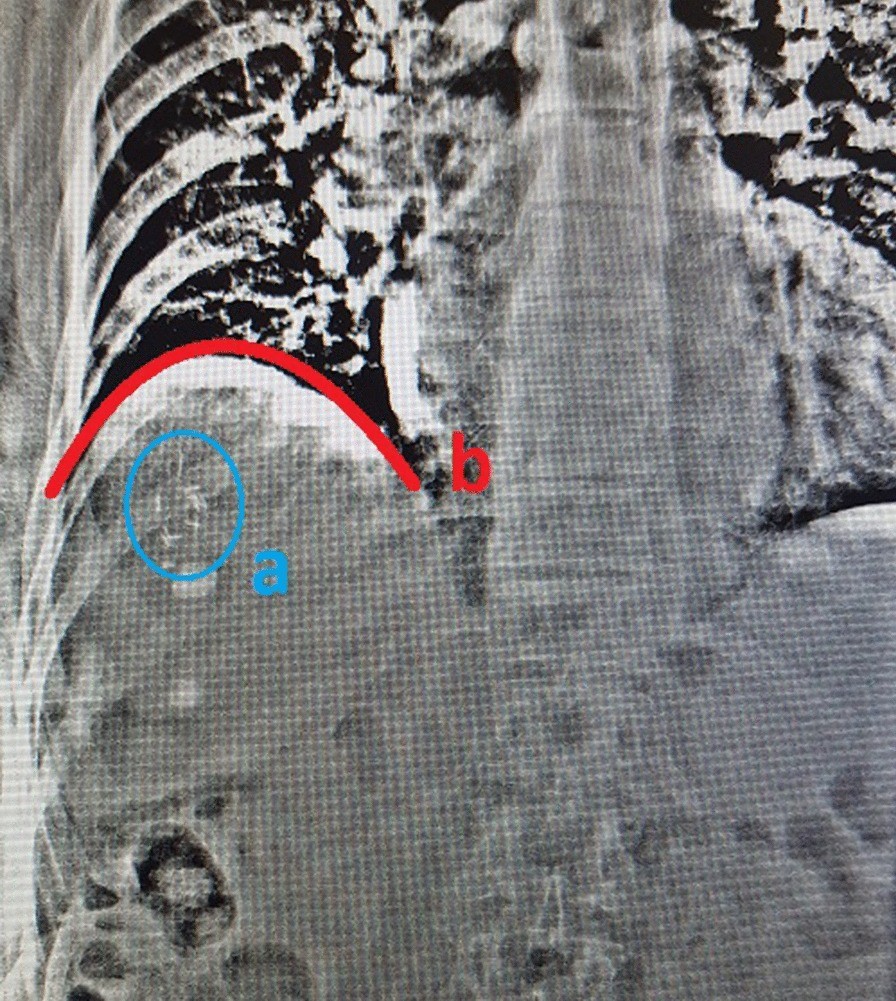

Fig. 3From: Protocol of a study investigating breath-hold techniques for upper-abdominal radiation therapy (BURDIE): addressing the challenge of a moving targetAP kV fluoroscopy image with fiducial markers (a—blue) and diaphragm position (b—red)Back to article page